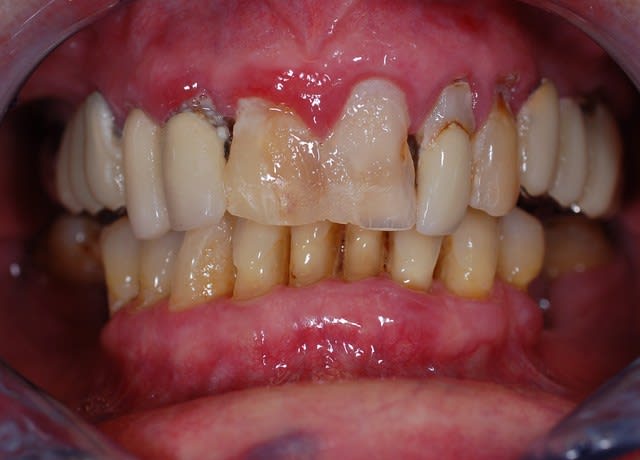

Je t envoie deux photos. Qu'en penses tu? Merci pour tes préceiux conseils

Photo damien dents 017 yunkol - Eugenol

Photo damien dents 019 pycbpi - Eugenol

L'image est floue, il n'y a pas assez de profondeur de champ : il faut donc fermer plus le diaphragme (F11 ou plus)

+1...f11 ou plus...et passer en mode manuel, avec sélection du SEUL collimateur central...là la mise au point se fait sur un collimateur périphérique....(le/les collimateurs utilisés sont en rouge lors de la map...et tu peux vérifier en modifiant les paramètres de lecture...tu peux faire afficher les collimateurs actifs...)...mais encore une fois...que le central pour la macro...